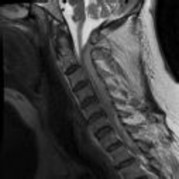

Preoperative MRI images are shown from a 67-year-old woman with neck pain, bilateral upper extremity paresthesias, progressively worsening balance, several falls, and increasing problems in both hands with dropping objects. Figure 1 is a sagittal view, Figure 2 is an axial cut at C2-3, Figure 3 is an axial cut at C5-6, and Figure 4 is an axial cut at C6-7. The patient’s motor strength is grade 4+ of 5 in the bilateral upper extremities.

What is the best next step?

4. Posterior decompression and fusion Discussion: D

The patient has degenerative changes with central and foraminal stenosis from C2-7, including spinal cord compression at C2-3, C5-6, and C6-7. Her progressively worsening balance, falls, and clumsiness are consistent with cervical spondylotic myelopathy. Given the progressive nature of the neurologic symptoms, surgery is recommended for patients with worsening

symptoms. Physical therapy potentially could provide pain relief but would not address the spinal cord compression. Cervical epidural steroid injection is not recommended because of the increased neurologic risk in the setting of substantial spinal cord compression. Given the multiple levels involved and the extension to the C2-3 level, an anterior approach would increase the risk of morbidity and pseudarthrosis compared with the posterior approach, which would allow adequate decompression of the central and foraminal stenosis.

Surgery for cervical myelopathy is performed to decompress the spinal cord, stabilize the spine, and prevent further neurologic injury. Most patients obtain considerable pain relief and some improvement in balance and clumsiness, depending on the severity of the symptoms. Complete resolution of all symptoms should not be expected.